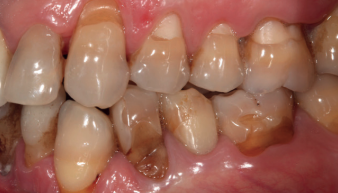

Cuando se produce la pérdida dentaria en la zona posterior del maxilar se genera habitualmente una disminución de la masa ósea disponible para la inserción de los implantes, a expensas de una neumatización del seno maxilar1. Esta pérdida de hueso puede ser mayor si los molares se encuentran afectados por patología periodontal avanzada, han presentado infecciones de repetición por diferentes causas, se han producido fracturas verticales, o cuando el tramo se mantiene edéntulo durante largo tiempo sin reponer los dientes ausentes2. La zona posterior del maxilar suele tener una menor densidad ósea de forma habitual, por lo que la rehabilitación con implantes dentales de estos sectores se complica cuando el volumen óseo residual en altura está muy disminuido y la densidad ósea también. En estas zonas, clásicamente se han empleado técnicas de elevación de seno, para poder colocar implantes en áreas de escaso volumen óseo en altura, pudiendo optar por la técnica “convencional” mediante ventana lateral, descrita por Tatum en los años 703, o a través de la propia cresta alveolar y del neoalveolo que se construye para insertar el implante, generándose de este modo una elevación transalveolar o transcrestal, descrita por Summers3,4 como un abordaje más conservador para el procedimiento de elevación de seno. La técnica de elevación crestal, es la opción más utilizada en la mayoría de las ocasiones, reservándose la elevación lateral para casos donde existe un volumen óseo residual menor de 5 mm donde se considera que la estabilización del implante en un área tan pequeña puede ser complicado.

En 2015, Anitua y cols.5 describen la realización de elevación de seno transcrestal mediante el uso de las mismas fresas que se emplean en la preparación del alveolo de los implantes cortos, unas fresas de corte frontal que retiran lentamente el suelo del seno sin dañar la membrana de Schneider, pudiendo realizar la elevación con mayor control y confort para el paciente, al evitar los osteotomos y las técnicas de percusión previas. Con este procedimiento y el uso de los implantes cortos y extracortos, se logra la rehabilitación de los sectores posteriores maxilares con extrema atrofia en altura y con elevadas tasas de éxito (96-98%)5-8. En el protocolo descrito por nuestro grupo de estudio, se pone de manifiesto la importancia del diagnóstico previo del hueso residual (altura, anchura, densidad y tipo óseo) y de la planificación del fresado para lograr la estabilidad tridimensional del implante y evitar micromovimientos en la fase inicial de la oseointegración9-11. Además, como último actor, se incorporan los implantes ultracortos de 4,5 mm de longitud, para dotarnos de una herramienta más para el abordaje de las atrofias verticales extremas12. Teniendo en cuenta todos estos parámetros, cobra mayor importancia la presencia de implantes extracortos y ultracortos para el abordaje del maxilar posterior atrófico, ya que una cuidadosa planificación de la cirugía que va a ser llevada a cabo nos permitirá la selección de estos implantes para nuestros casos logrando los mejores resultados5,12 Nuestro grupo de estudio ha preconizado en varios trabajos de investigación la utilidad de la estabilización primaria del implante de forma tridimensional, olvidando el concepto del anclaje apical, para ser sustituido por las paredes laterales del seno en este caso y las corticales vestibular y palatina del hueso residual5-8. De esta forma se ha logrado con éxito rehabilitar zonas posteriores del maxilar con extrema atrofia con implantes extracortos, aun cuando el volumen óseo residual era por debajo de 5 mm, que como hemos visto anteriormente era la distancia límite en la que muchos autores fijan la altura ósea para determinados procedimientos de implante y elevación transalveolar simultánea2-4. En el presente trabajo, se presenta un estudio retrospectivo en el que se han evaluado implantes de 4,5 mm de longitud, insertados en sectores posteriores maxilares con una altura ósea residual igual o menor a 3 mm, realizándose al mismo tiempo una elevación de seno transcrestal. Con ello, se quiere analizar el comportamiento de estos implantes en situaciones muy extremas, donde la recomendación actual generalizada en la literatura internacional sería la elevación de seno convencional y la colocación de implantes en un segundo tiempo.

En la Figura 2 se muestran los diámetros y longitudes de los implantes incluidos en el estudio en función de los milímetros de cresta ósea residual en altura. La densitometría media de la zona de inserción del implante del grupo fue de 293,33 HU (+/- 144,99). El torque medio de los implantes estudiados fue de 27,33 Ncm (+/- 16,99). Todos los implantes se cargaron en dos fases quirúrgicas y en todos se llevó a cabo una elevación de seno transcrestal con injerto óseo autólogo particulado obtenido del fresado, embebido en PRGF-Endoret como marterial de injerto. En ninguno de los casos se registraron complicaciones relativas a la cirugía. Los implantes presentaron un seguimiento medio de 13,33 meses tras la carga (+/- 3,09), no encontrándose complicaciones ni fracasos durante este tiempo de seguimiento, por lo que la supervivencia fue del 100%. Todos los implantes fueron rehabilitados mediante prótesis múltiple atornillada mediante elemento intermedio (transepitelial múltiple, Multi-im®), encontrándose dos de los implantes ferulizados a otros de la misma longitud (4,5 mm) y el resto a longitudes mayores. La ratio corona-implante medio para el grupo de estudio fue de 2,43 mm (+/-0,45). La pérdida ósea mesial final media de todos los implantes fue de 0,42 mm (+/- 0,51) y la pérdida ósea distal final media de 0,16 mm (+/-0,34). En las Figuras 3 –13 se muestra uno de los casos incluidos en el estudio.